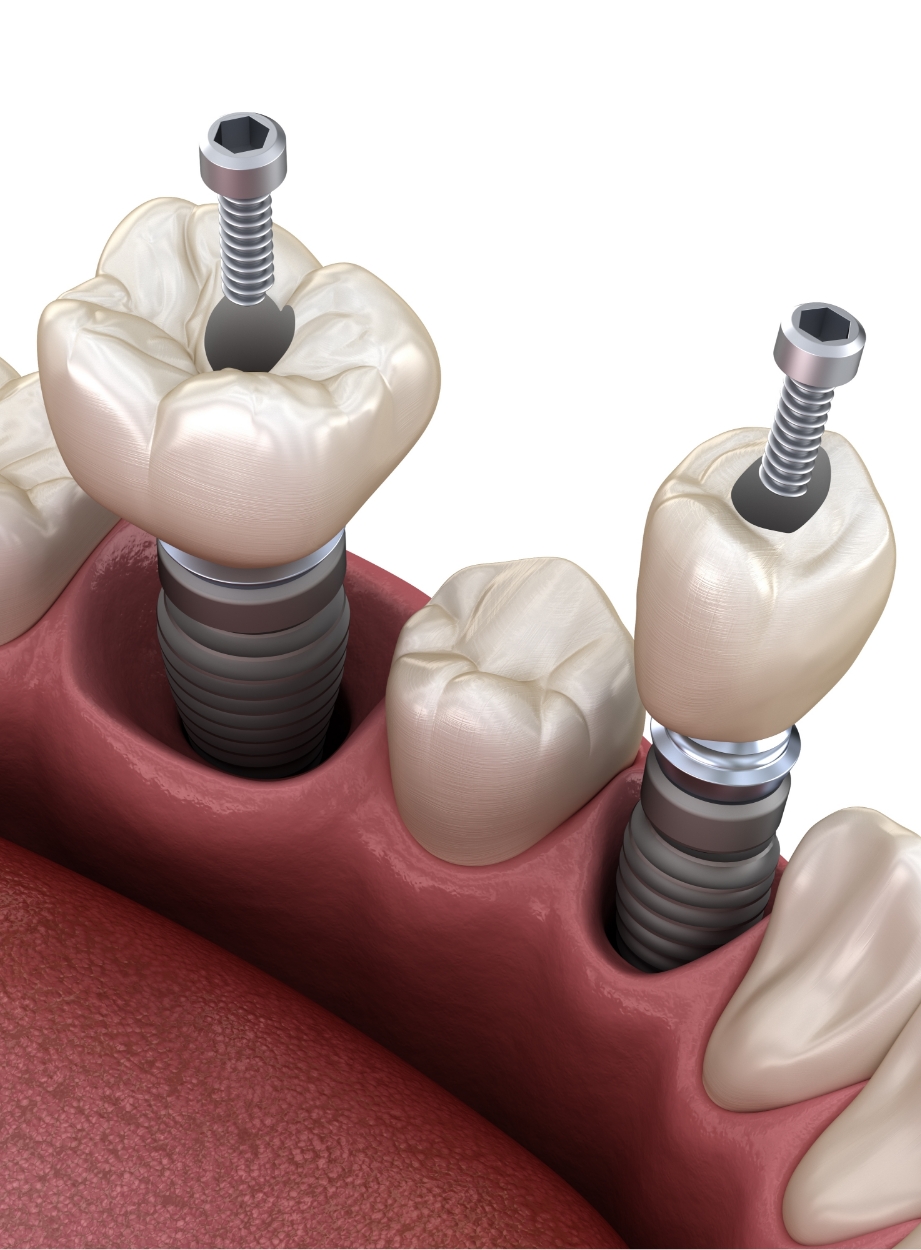

种植牙是在精准诊断与治疗计划的基础上,

通过多个步骤进行的治疗方式

会根据患者的口腔状况, 分阶段安全推进

根据患者状况,

应用个性化种植牙设计

按照预定导板,

稳定植入种植牙